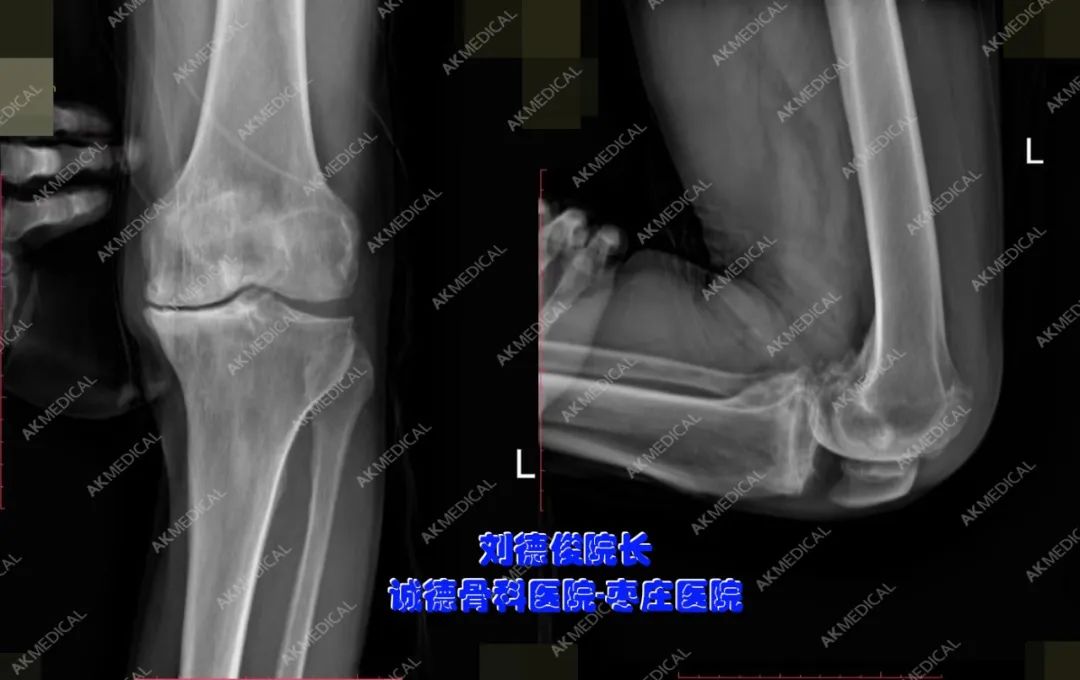

患者信息:67歲,男性,40年前無(wú)明顯誘因出現(xiàn)雙膝疼痛,間斷發(fā)作,勞累后加重,休息可緩解,負(fù)重時(shí)疼痛明顯,左膝關(guān)節(jié)尤為嚴(yán)重,曾行關(guān)節(jié)腔注射及貼膏藥治療,療效不佳,40年來(lái)疼痛反復(fù)交替出現(xiàn)。疼痛加重時(shí)無(wú)法行走。

診斷:左側(cè)膝關(guān)節(jié)骨性關(guān)節(jié)炎。

左側(cè)膝關(guān)節(jié)術(shù)前正側(cè)位X光片

左側(cè)膝關(guān)節(jié)術(shù)后正側(cè)位X光片